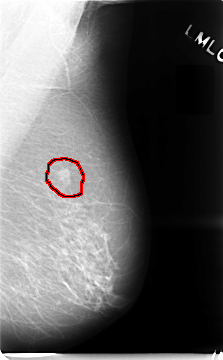

C_0018_1.LEFT_MLO

LEFT_MLO LINES 4672 PIXELS_PER_LINE 2888 BITS_PER_PIXEL 12 RESOLUTION 50 OVERLAY

FILE: C_0018_1.LEFT_MLO.OVERLAY

TOTAL_ABNORMALITIES 1

ABNORMALITY 1

LESION_TYPE MASS SHAPE LOBULATED MARGINS SPICULATED

ASSESSMENT 5

SUBTLETY 5

PATHOLOGY MALIGNANT

TOTAL_OUTLINES 1

BOUNDARY